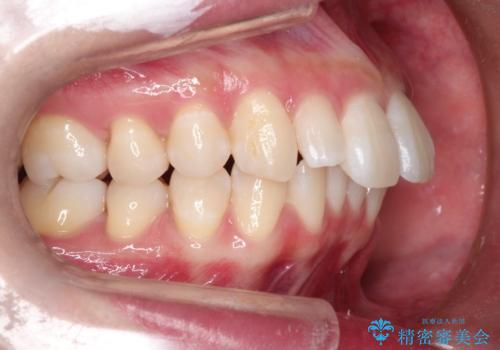

- 出っ歯と全体をきれいにしたいとのことで来院されました。

上顎の歯が全体的に前方に位置しているのと、前から2番目の歯が通常よりも小さい矮小歯という状態でした。

出っ歯をなおすために上顎の前から4番目の歯を抜歯して、引っ込めるのと、前から2番目の歯に通常の大きさのオールセラミックを装着して整った歯並びにすることにしました。